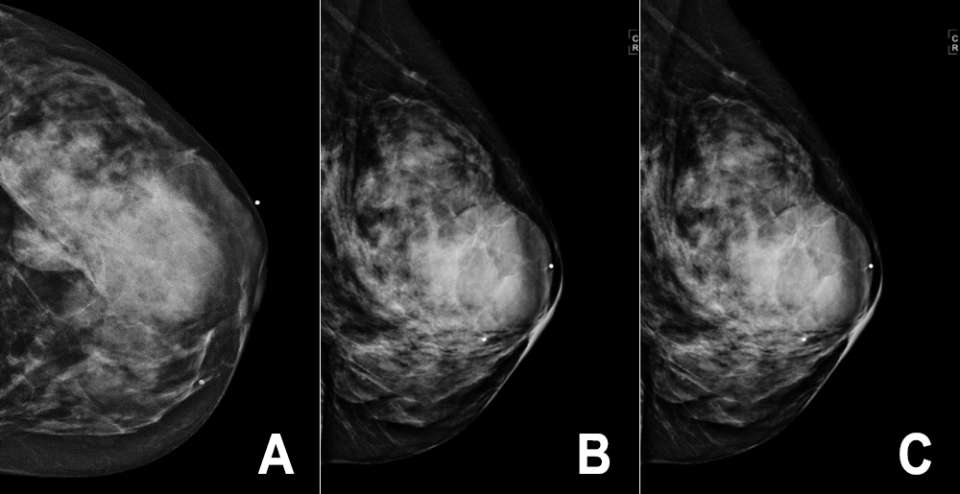

Mammography

There are no pathognomonic imaging features for breast sarcoma on any imaging modality and imaging findings are widely variable. Mammographically, breast sarcomas are described as round, oval, or irregular masses with microlobulated or indistinct margins3. They demonstrate high density compared to the surrounding breast fibroglandular tissue (Figure 1). A less common mammographic finding is architectural distortion, and there are infrequently associated microcalcifications. In fact, the lack of microcalcifications may serve as a clue to include sarcoma in the differential diagnosis1,4.